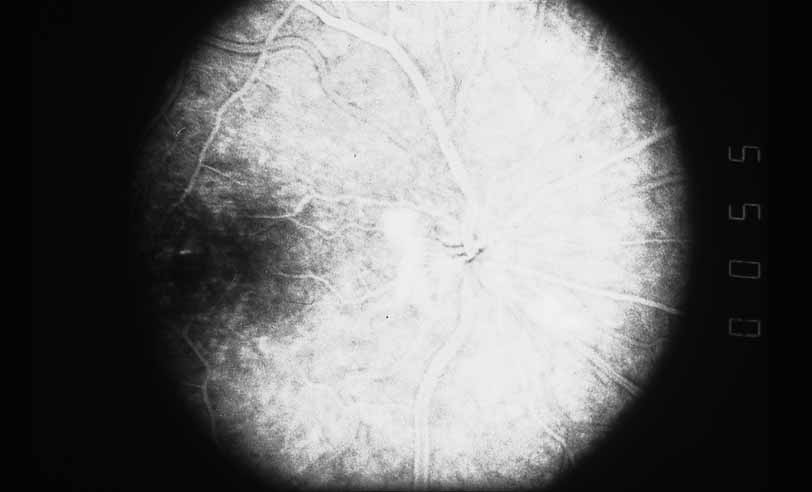

Fig. 1 Serpiginous choroiditis. Early frame of the fluorescein angiogram shows hypofluorescent and hyperflourescent patches extending outward from the optic nerve in a serpiginous pattern (Courtesy of Joseph Michaelson).

Fig. 2 Serpiginous choroiditis. Late frame of the fluorescein angiogram shows extensive staining of previously hypofluorescent zones, with continued hypofluorescence, characteristic of the acute phases of serpiginous choroiditis (Courtesy of Joseph Michaelson).